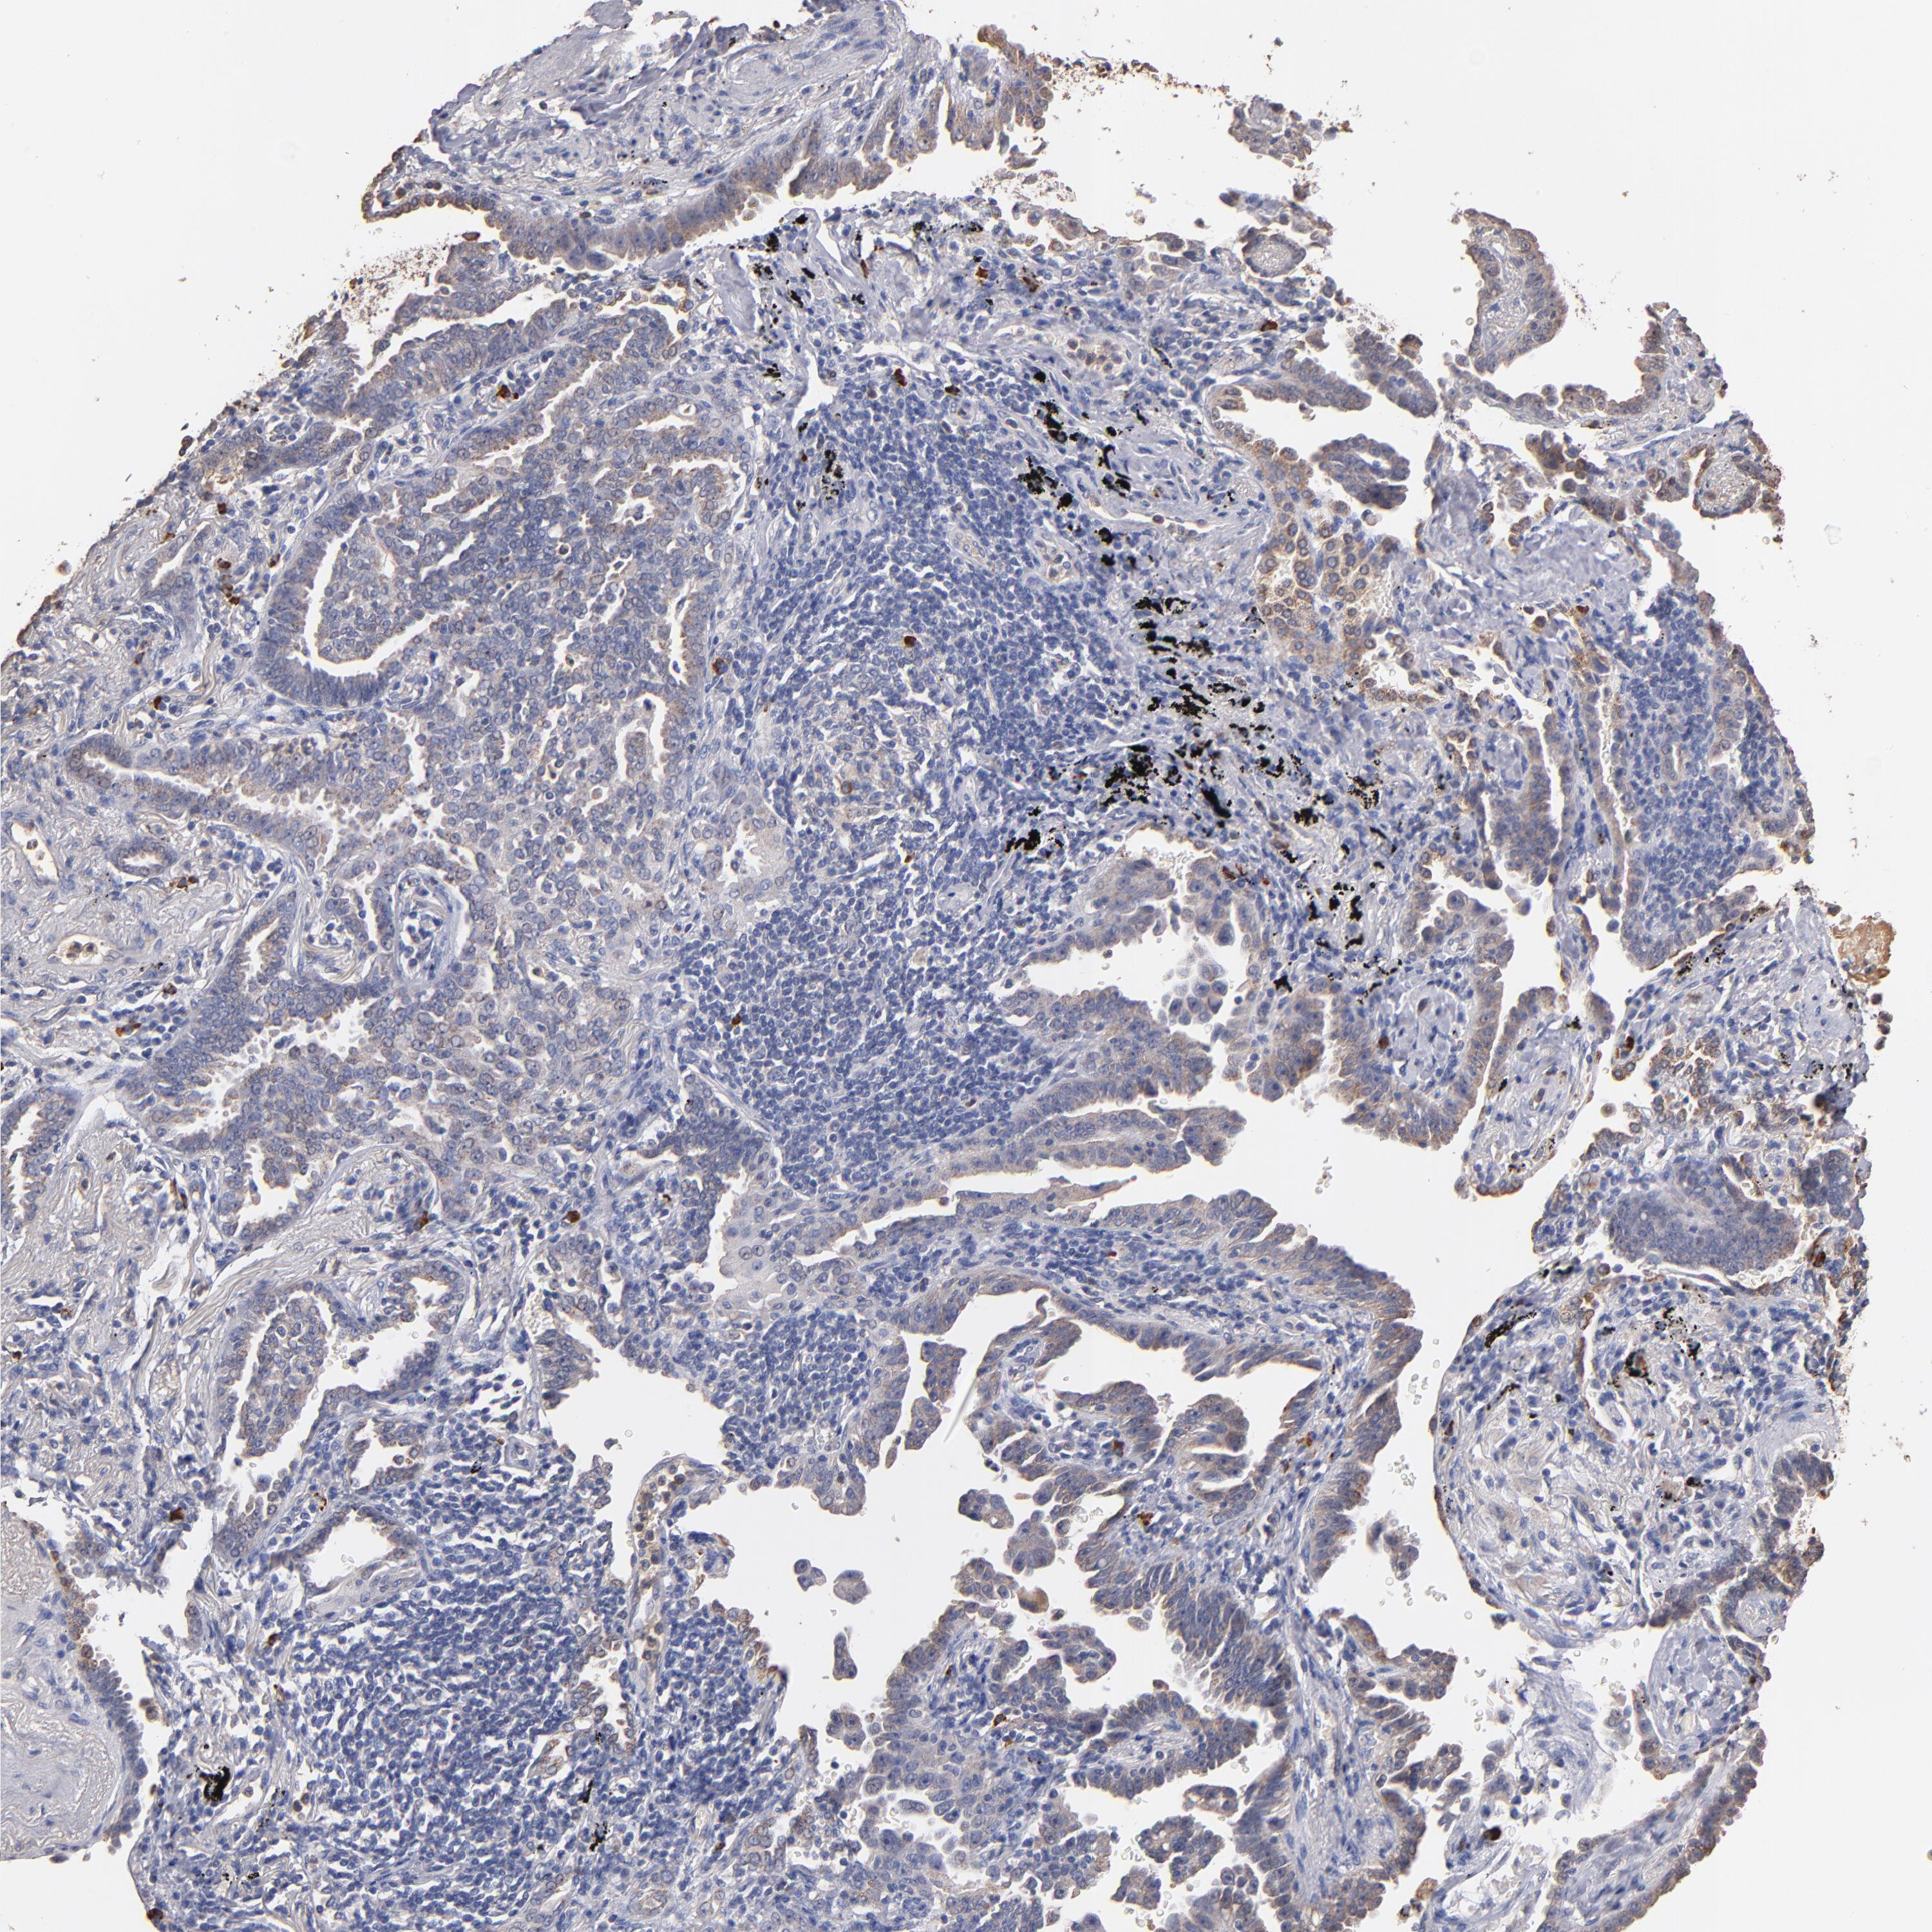

CANCER LUNG CANCER Show tissue menu

LUAD TCGA LUAD VALIDATION LUSC TCGA LUSC VALIDATION PROTEIN LUAD CPTAC PROTEIN LUSC CPTAC PROTEIN EXPRESSION

Lung cancer

Human cancer

Lung adenocarcinoma

Lung squamous cell carcinoma